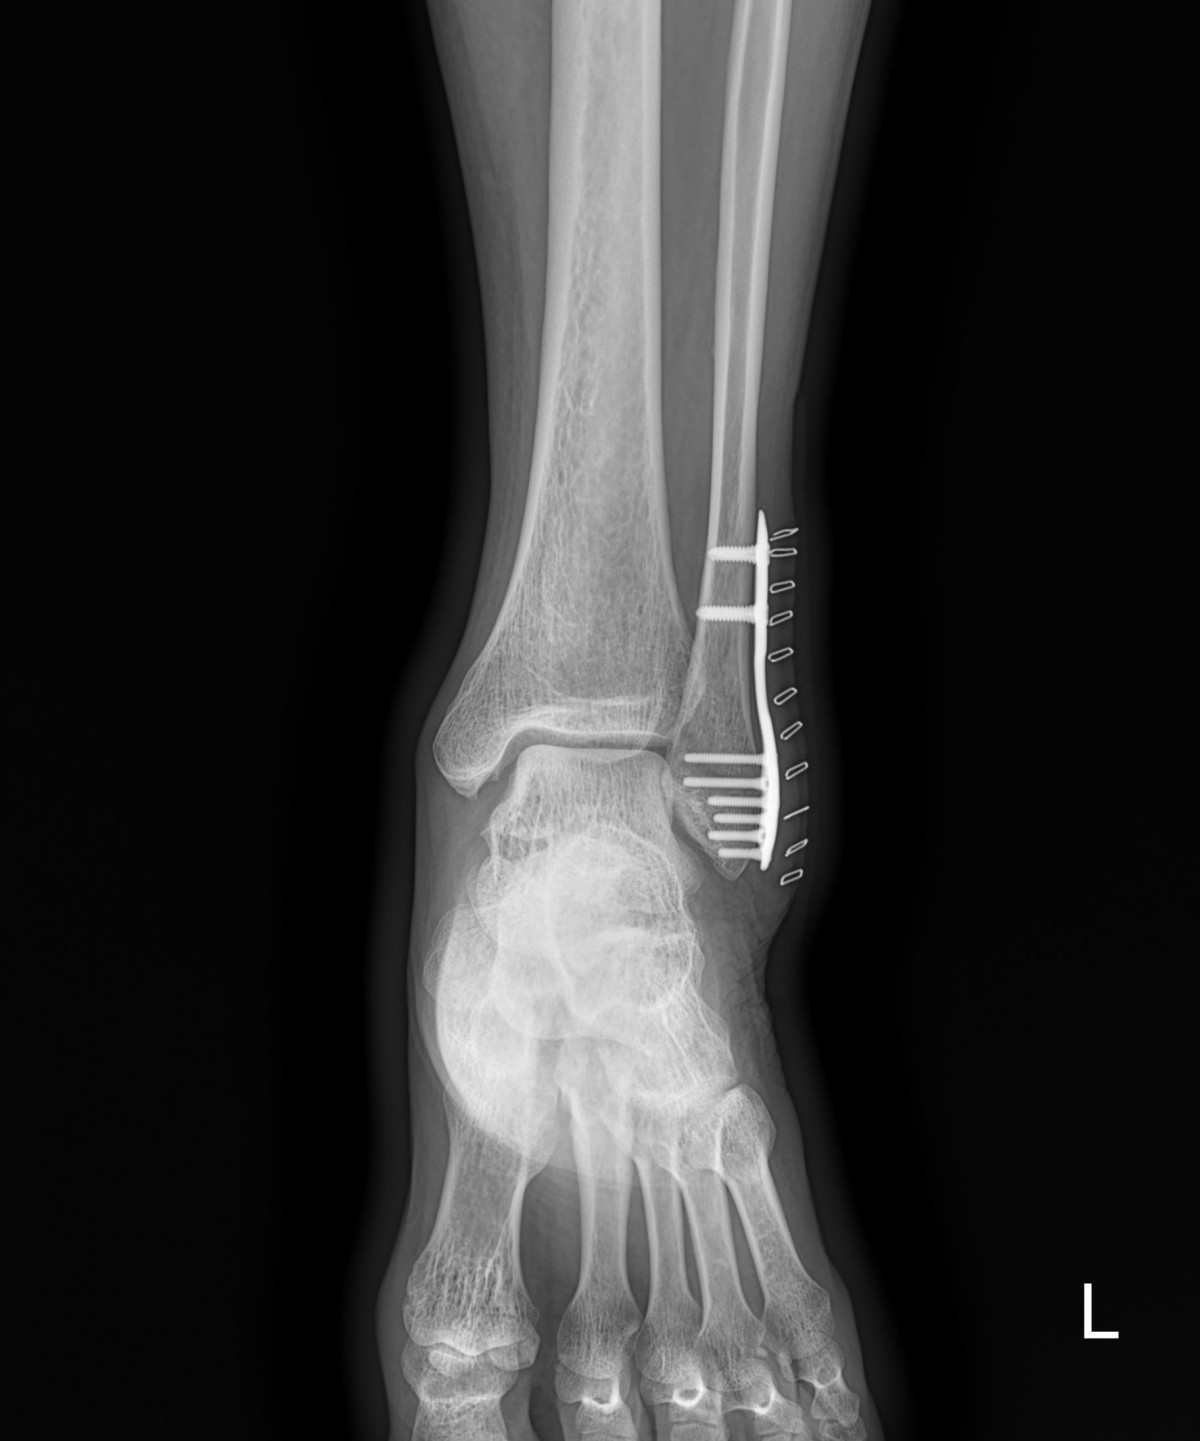

이재상원장님 발목골절수술 (4610)신재O 환자

작성자 최고관리자 댓글 0건 조회 1,243회 작성일 22-05-09 12:32